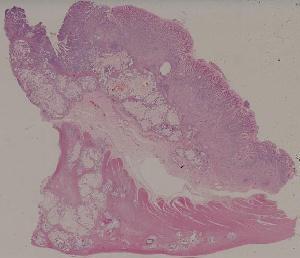

60. Gastric ulcer

61. Gastric adenocarcinoma(Mucinous adenocarcinoma of the stamoch)

62. Acute viral hepatitis (common type)

63.Chronic active viral hepatitis

64. Acute fulminant viral hepatitis

65. Subacute fulminant viral hepatitis

66. Active nodular cirrhosis of the liver

67. Inactive nodular cirrhosis of the liver

68. Biliary fibrosis

69. Hepatocellular carcinoma

72. Membranous glomerulonephritis

73. Acute glomerulonephritis

74. Crescentic glomerulonephritis

75. Chronic glomerulonephritis